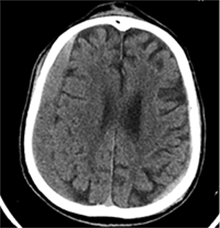

53 m. vyras sumuštas gatvėje ir greitosios medicinos pagalbos atvežtas į Priėmimo skyrių. Pacientui atlikta galvos kompiuterinė tomografija (GKT). Rasta: poūmė, stora, apie 16 mm dydžio subdurinė hematoma (SDH) dešinėje pusėje konveksitaliai ir ūmi nedidelė SDH kairėje pusėje frontoparietaliai. Vidurio struktūrų dislokacija (VSD) į kairę – minimali. Kairėje – kaukolės skliauto linijinis lūžis. Nustatyta nosies kaulų, nosies pertvaros, dešiniojo viršutinio žandikaulio kaktinės ataugos ir kūno, sinuso sienelių lūžių, dešinės akiduobės medialinio krašto lūžių ir dešiniojo skruostinio lanko lūžių (1 pav.). 2020 m. liepos mėn. pacientas skubos tvarka operuotas: atlikta dešinė kraniotomija, pašalinta hematoma. Atlikus kontrolinę GKT, buvo matyti, kad pašalinta didžioji hematomos dalis (2 pav.). Pacientas konsultuotas veido ir žandikaulio chirurgo, skubus chirurginis gydymas neindikuotas. Praėjus 3 savaitėms, pacientas, esant gerai funkcinei ir neurologinei būklei, tolesnio gydymo perkeltas į slaugos ligoninę, vėliau išleistas gydytis ambulatoriškai.

1 pav. Prieš pirmąją operaciją (poūmė, stambi, iki 16 mm SDH apie dešinįjį pusrutulį, ūmi nedidelė SDH kairėje F-P; VSD į kairę ~3 mm)